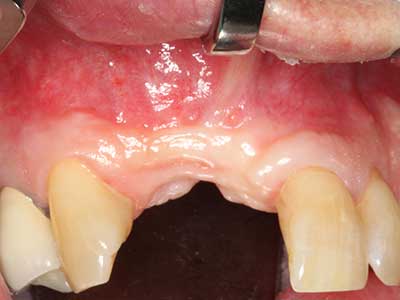

Fig. 12: dopo sei mesi di processo di guarigione, la cresta alveolare è vitale e sufficientemente dimensionata in tutti i piani.